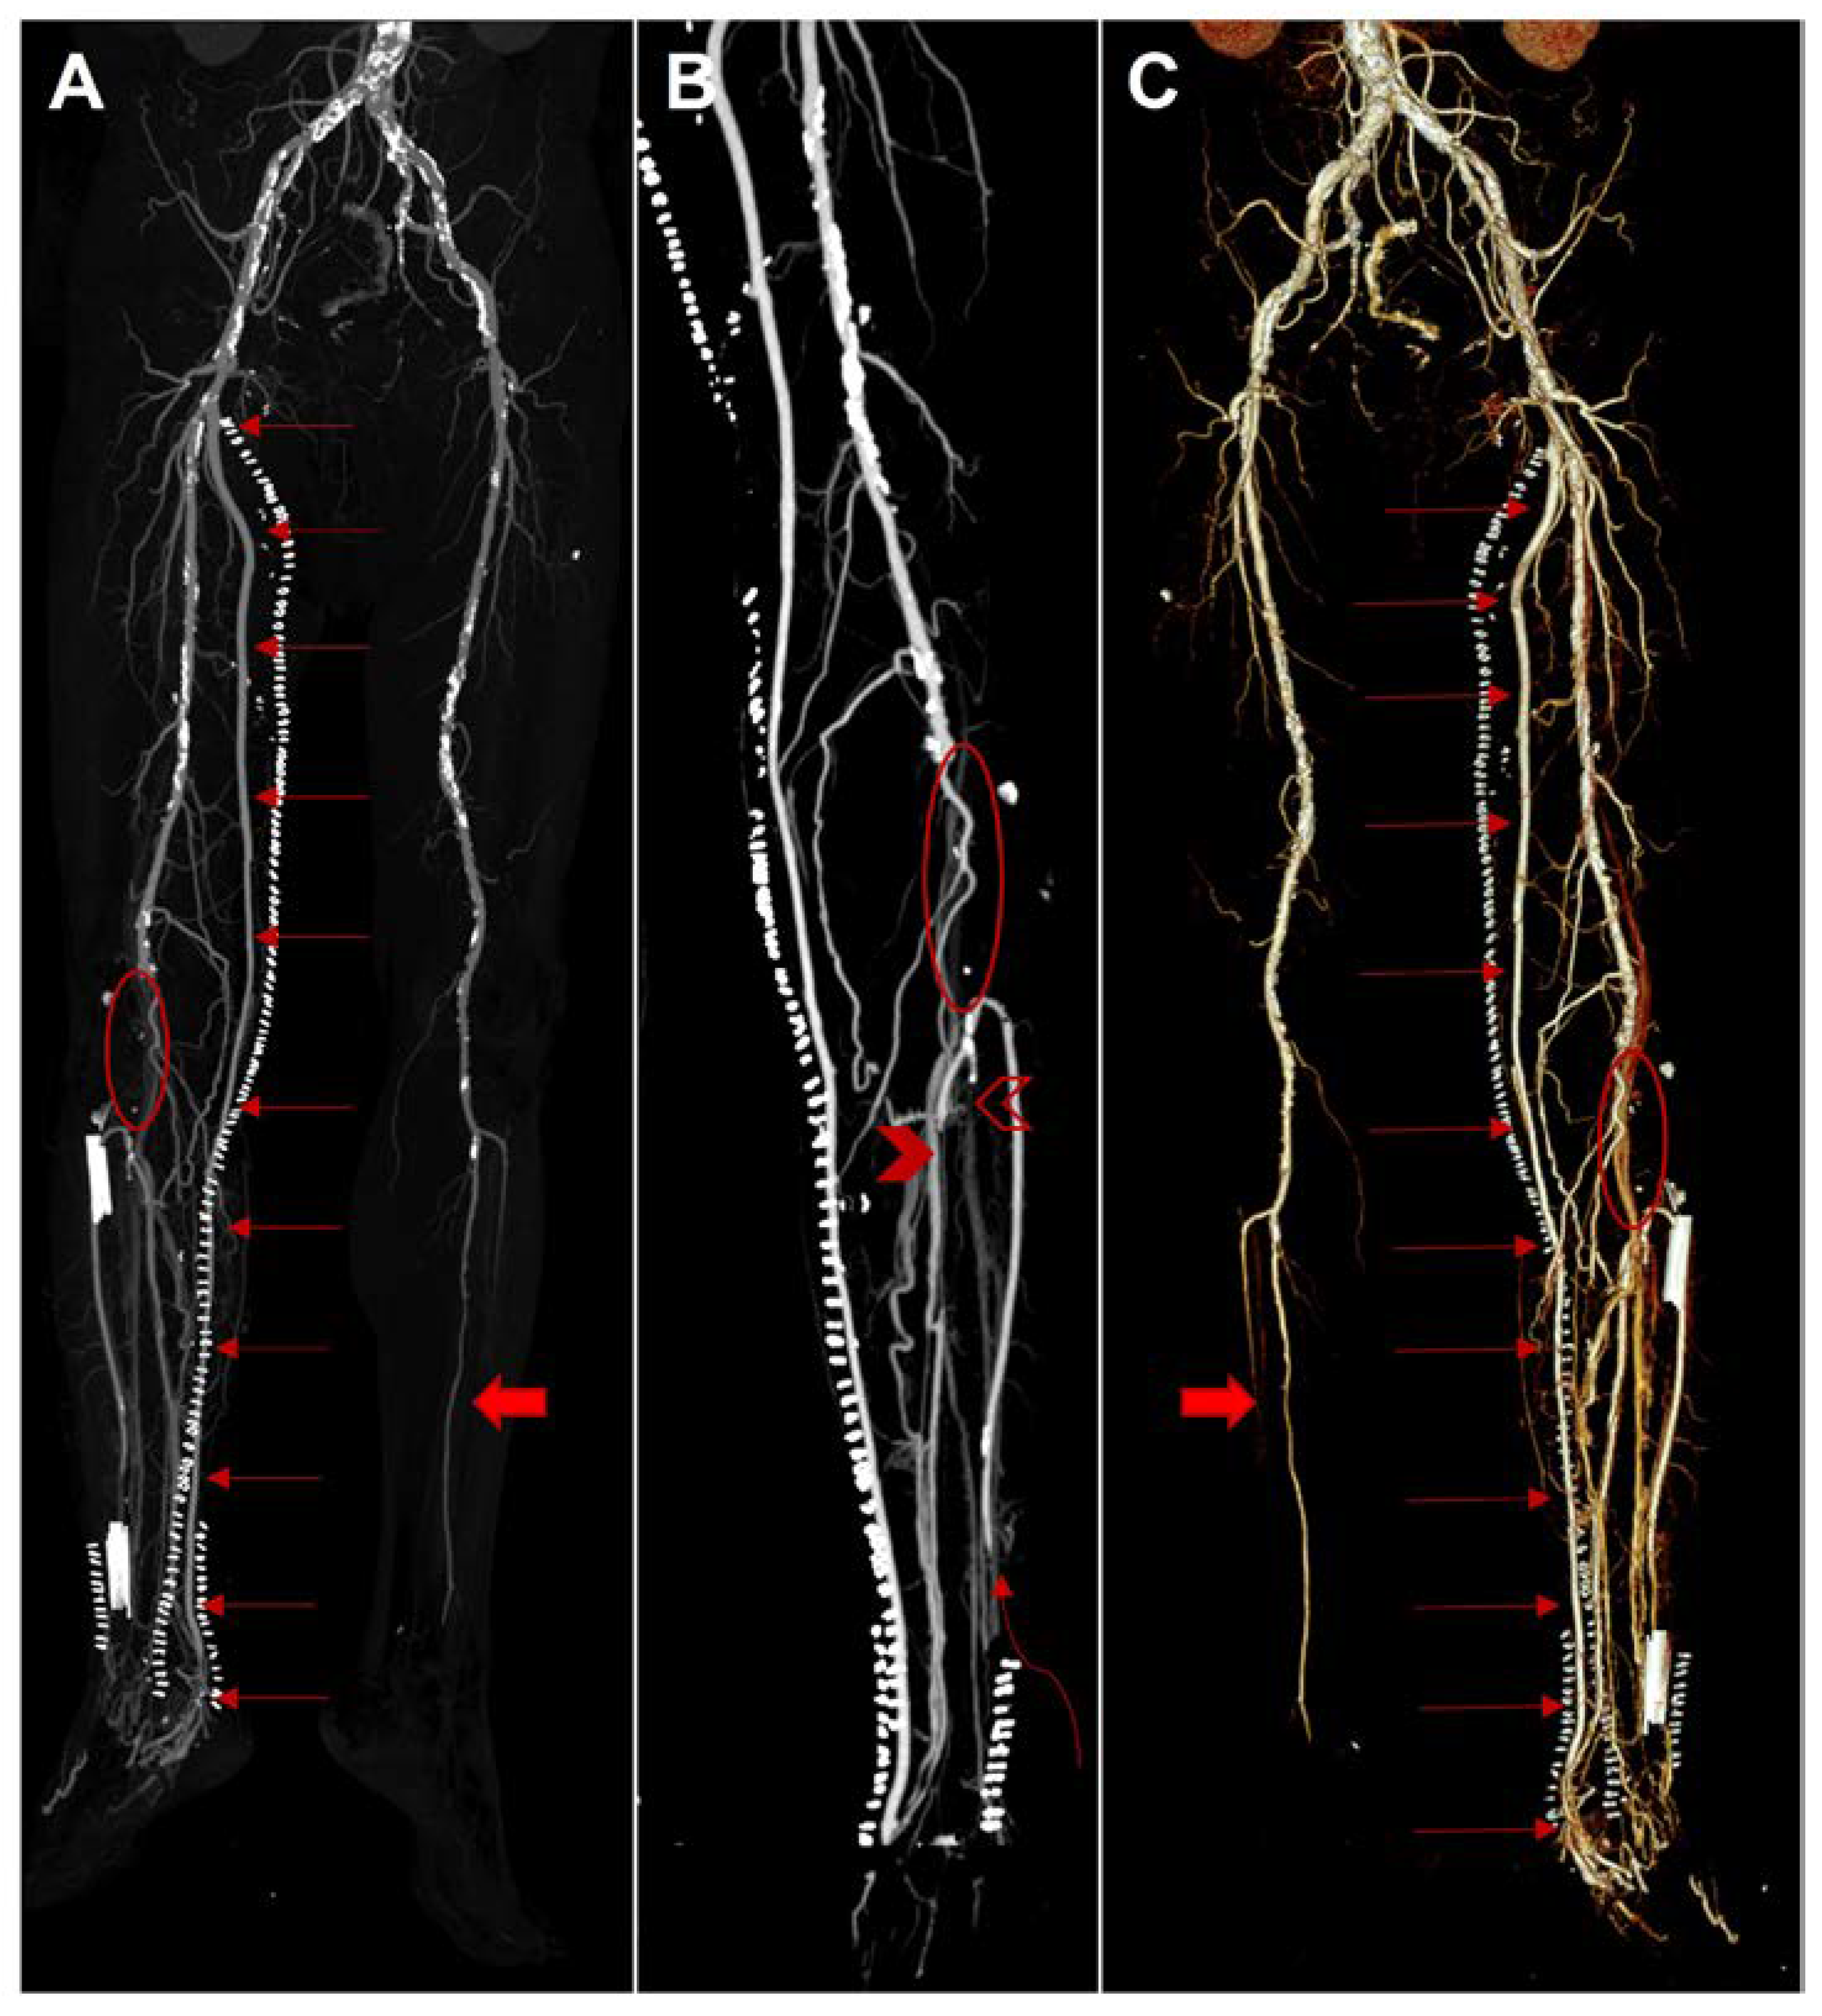

Conversion of Femoral-Tibial Bypass Surgery into Deep Vein Arterialization in a Patient with Severe Peripheral Artery Disease: Post-Operative Computed Tomography and Angiography Findings

2. Case Description

Parillo, M.; De Stefano, D.; Catanese, V.; Mallio, C.A.; Spinelli, F.; Stilo, F.; Quattrocchi, C.C. Conversion of Femoral-Tibial Bypass Surgery into Deep Vein Arterialization in a Patient with Severe Peripheral Artery Disease: Post-Operative Computed Tomography and Angiography Findings. Hearts 2023, 4, 12-19. https://doi.org/10.3390/hearts4010002